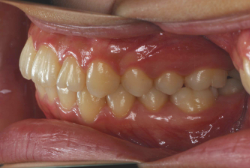

「出っ歯を治したい」という主訴で来院したケースです。診断の結果、「2級1類の上顎前突+軽度叢生」と判明しました。2級というのは、基本的に出っ歯の噛み合わせになっていることを言います。その中でも上の前歯が著しく外に反っているケースを、「1類」といいます。初診時の横向きの写真を見ると、それがはっきり分かります。上の前歯に押されて唇も膨らんで、審美線をかなりオーバーしています(審美線とは、鼻の先端と顎の先端を結ぶ線のことで、この線よりも唇は内側にある方が良いとされています)。

このような症状の場合は、前歯を内側に入れるためにかなり大量の隙間を必要とします。通常は上下左右の小臼歯を抜歯させていただくのが正解です。治療後は歯の角度が正しくなっただけでなく、唇の審美性が大幅に改善しました。もちろん噛み合わせ的にも正しい状態が確立しています。